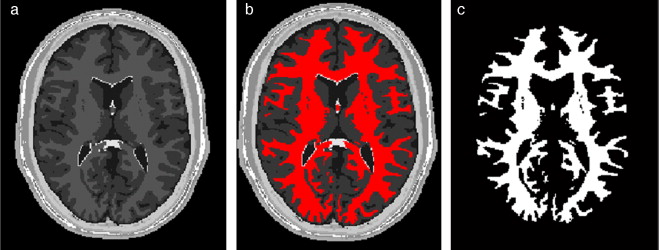

En la figura 20 se presentan los resultados obtenidos por cada etapa en imágenes médicas de IRM del cerebro en formato DICOM, 60 slices , tamaño de 256 × 256 pixels, voxel spacing: 0,86 × 0,86 mm × 3,0 mm . Por efectos de visualización, solamente se presenta uno de los cortes axiales utilizados. Obsérvese en la figura 20 .b la selección de cuatro semillas sobre la zona de interés, las cuales fueron asignadas de manera arbitraria. El éxito de la segmentación dependerá del lugar donde se coloquen estas semillas.

Segmentación de materia blanca empleando Region Growing en IRM del cerebro. (a) ...

Figura 20.

Segmentación de materia blanca empleando Region Growing en IRM del cerebro. (a) Volumen de IRM cerebral original. (b) Vista de un corte axial con la lección de cuatro semillas iniciales. (c) Imagen (b) filtrada con difusión anisotrópica. (d) Vista del corte axial (b) con la materia blanca segmentada a través de Region Growing . (e). Vista volumétrica de la materia blanca segmentada en (d).